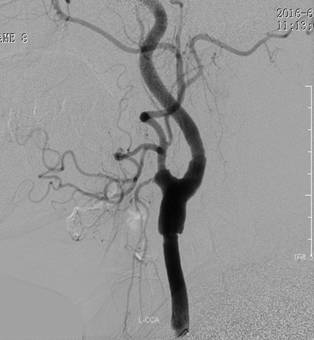

1周前,郭大姐再次发生右侧肢体无力的症状,于是家人将她送到广东三九脑科医院神经内科就诊,入院后积极完善相关检查,颅脑DWI显示:1、左侧基底节区、大脑脚及桥脑右侧、右侧枕叶多发陈旧性脑梗塞,2、考虑胼胝体压部偏左侧脑梗塞(偏慢性期)(如图1、图2)。DSA检查提示:1. 基底动脉末端闭塞,双侧大脑后动脉、后交通动脉未见显影,双侧大脑中动脉经皮层软膜动脉向同侧枕叶代偿供血;2. 双侧颈内动脉起始部重度狭窄(如图4、图5),狭窄率约90%,狭窄长度约20px;3.双侧椎动脉起始部中度狭窄,狭窄率约50%;4. 脑动脉硬化,颅内动脉走行僵硬,呈不同程度狭窄。

图 4 术前DSA提示:左侧颈内动脉起始部放大;

图 5 术前DSA提示:右侧颈内动脉起始部放大;